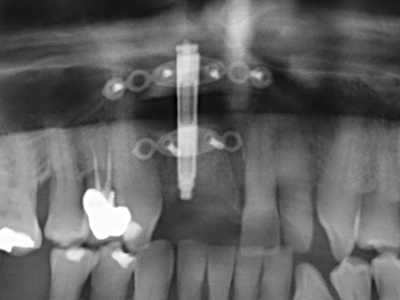

Abb. 11: Das postoperative OPTG veranschaulicht die vertikale Augmentation und Sinusbodenelevation.

Abb. 13: Bei diesem 52-jährigen Patienten ist bei 4 mm UK-Restknochenbreite während des Bone Splittings auf eine ausreichende Wasserkühlung zu achten.

Abb. 14: Einbringung von vier konischen RSX-Implantaten (Bego Implant Systems, Bremen).

Abb. 15: Die röntgenologische Ein-Jahres-Kontrolle zeigt stabile Verhältnisse des Knochenniveaus.